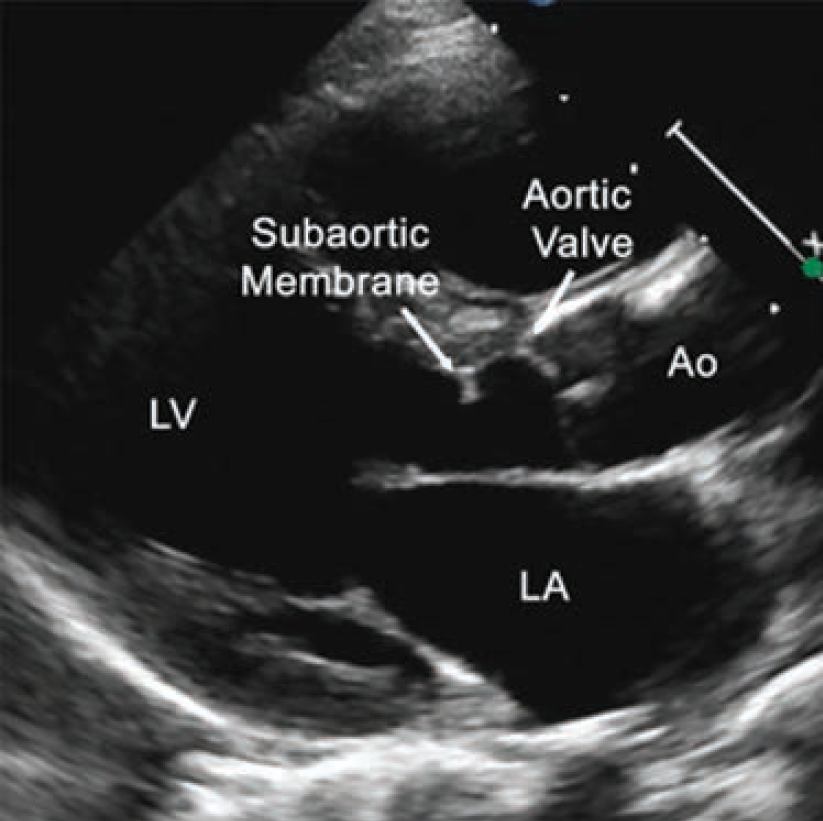

A 64-year-old female presented to the valve clinic with increasing shortness of breath, dizziness, and multiple implantable cardioverter-defibrillator (ICD) shocks over 4 months. She required 2 liters of nocturnal O2 and had a fall with significant head trauma due to syncope. She was referred to the valve clinic for consideration of a percutaneous treatment option for a subaortic membrane. She was a poor surgical candidate due to three prior sternotomies from prior valve replacements. Additionally, she presented with chronic atrial fibrillation, a history of stroke, a thromboembolic disorder, and a left ventricular outflow tract (LVOT) gradient of 80 mmHg. A transesophageal echocardiogram (TEE) revealed that she had an ejection fraction (EF) of 20% (Figure 1). Her case was complex and high risk.

Baseline computed tomography imaging revealed the patient had an enormous left atrium (volume of 798 cm3), a narrow LVOT, and an 8.5 mm subaortic membranous band. The team determined that multimodality imaging (TEE, transthoracic echocardiogram [TTE], and intracardiac echocardiography [ICE]) would be required for an endovascular fix due to shadowing artifacts from the mechanical mitral valve and the tricuspid ring, as well as distortion from the large left atrium.

The procedure was evaluated by TEE, TTE, and ICE (Video 3), ensuring its success. These imaging modalities showed no pericardial effusion or apparent damage to the aortic valve. Further, post-procedure hemodynamics demonstrated no residual gradient (Figure 2).

Post procedure, the patient had no complications and experienced significantly improved symptoms. At her 6-week follow-up appointment, the patient was no longer short of breath, had no additional ICD discharges, no syncopal episodes, and her EF had improved to 35%-40% (Figure 3; Video 4). She was discharged to her referring out-of-state cardiologist.